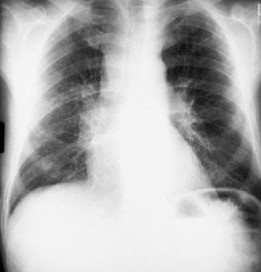

A chest x-ray and CT scan of the chest (Panel A) and a CT scan of the abdomen

and a barium-enema examination of the small bowel (Panel B) are shown below.

Panel A.

The chest x-ray shows widening of the superior mediastinum, aorticopulmonic window, hilar regions, and subcarinal region (left image). The CT scan shows diffuse widening of the mediastinum and hilar regions by low-attenuation fatty tissue (right image).